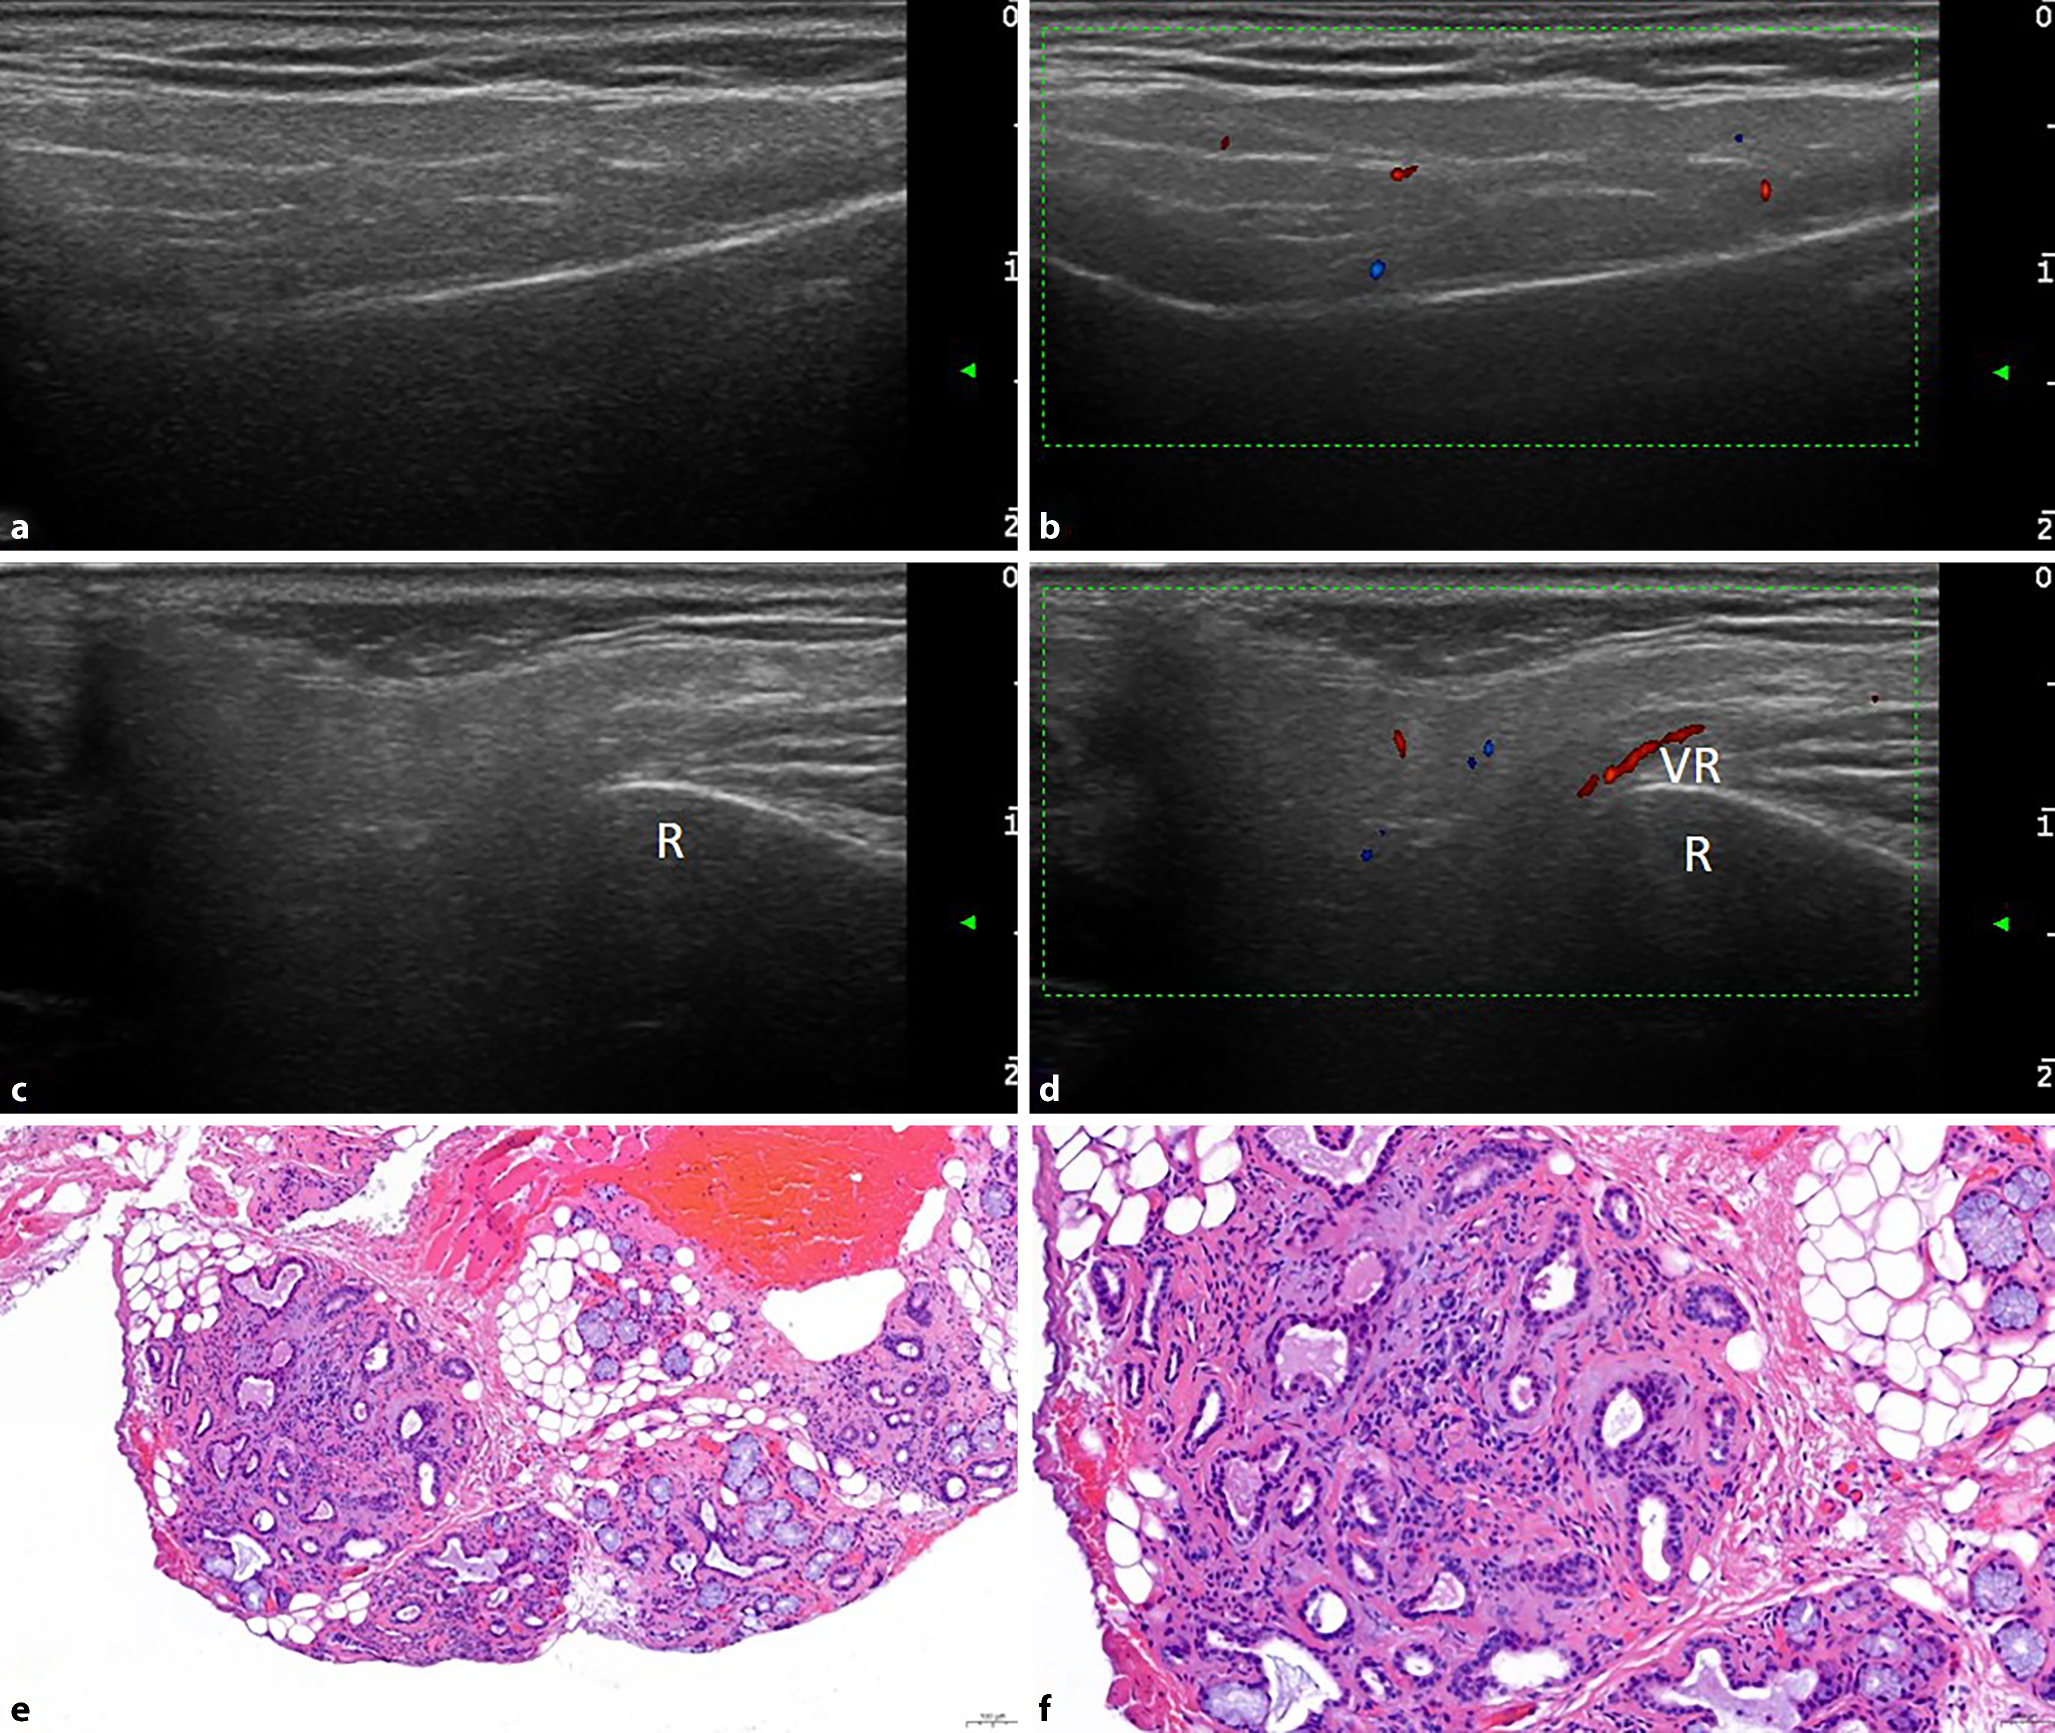

Der ANA(antinukleäre Antikörper)-Titer war stark erhöht, und es konnten Anti-SS-A-Antikörper (Ak) nachgewiesen werden. Sonographisch zeigten sich die PD sowie die SMD deutlich vergrößert mit hypoechogenen Foci im gesamten Drüsengewebe, entsprechend III°-Veränderungen sowie einer Hypervaskularisierung im Color-Doppler I° (entsprechend einer leichten Durchblutungssteigerung des Drüsengewebes; Abb. 1a–d). Im Rahmen eines Studienscreenings wurde außerdem eine SDB durchgeführt. Die Histologie ergab ein für ein primäres SS typisches Muster mit einer periduktal betonten lymphoplasmazellulären und histiozytären Infiltration mit teils konfluierenden Foci (Abb. 1e, f), sodass wir in der Zusammenschau aller Befunde den Verdacht auf primäres SS bestätigen konnten. Der Tränenfluss war leicht und die Speichelflussrate deutlich reduziert, sodass wir der Patientin eine symptomatische Therapie mit hyaluronsäurehaltigen Augentropfen und künstlichem Speichel empfahlen. Zudem erfolgte angesichts der hohen Krankheitsaktivität die Therapieeinleitung mit gewichtsadaptiertem Hydroxychloroquin und Methotrexat. Details s. Tab. 1.

Abb. 1

Sonographischer (ad) und histologischer Befund (ef) von Patientin 1 mit primärem Sjögren-Syndrom. Parotisdrüse longitudinal im B‑Bild (a) und Color-Doppler(CD)-Bild (b) sowie transversal im B‑Bild (c) und Color-Doppler-Bild (d). Deutliche echoarme Foci im gesamten Areal der Parotisdrüse (B-Bild III°). Es liegt eine leichte Hypervaskularisierung vor (CD-Bild I°). e, f Biopsie der kleinen Speicheldrüsen im Bereich der Unterlippe. Histologisch zeigt sich muköses Speicheldrüsenparenchym mit insbesondere periduktal liegenden, lymphoplasmazellulären und histiozytären Aggregaten (schwarze Pfeile). Wenn ein solches Aggregat mehr als 50 Zellen überschreitet wird von einem Fokus gesprochen. Das histologische Bild entspricht bei multiplen, stellenweise konfluierenden Foci einem Focus-Score 12